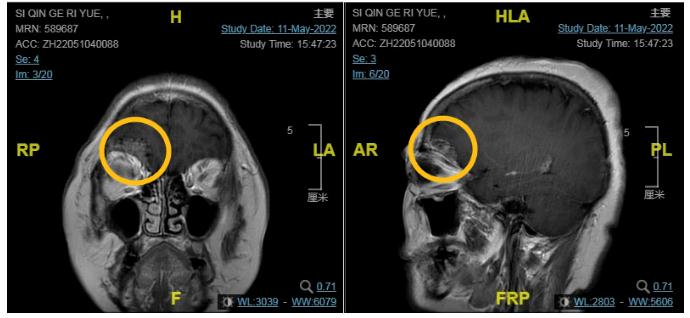

术前影像

经过多方咨询和朋友推荐,刘女士慕名来到包头医学院第一附属医院神经外科求治,侯晓峰医生通过影像学资料及症状,考虑肿瘤性质为脑膜瘤,并了解了刘女士的诉求与实际病情,从医学美学角度来衡量,手术除了要成功切除病灶,也要尽可能保护患者的外观,经过缜密的评估,侯晓峰团队决定为刘女士实施经眉弓的微创锁孔手术。